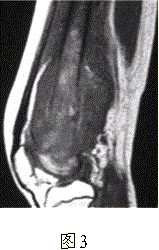

问题 患者男,16岁,左大腿下部疼痛伴肿胀2个月,逐渐加重。自感左膝上方胀痛,尤以夜间为著,伴行走困难。既往史及家族史无特殊。查体:左大腿下部明显肿胀,皮温较对侧升高。碱性磷酸酶明显增高。股骨平片及MRI见下图。 你认为对定性诊断有价值的征象是

选项 A.病变边缘模糊,内部信号不均 B.病变边缘骨皮质完整 C.病变周围可见软组织肿块 D.病变边缘可见骨膜反应,Codman三角形成 E.MR示病变周围骨髓明显水肿 F.病变内未见钙化影

答案 ACDEF